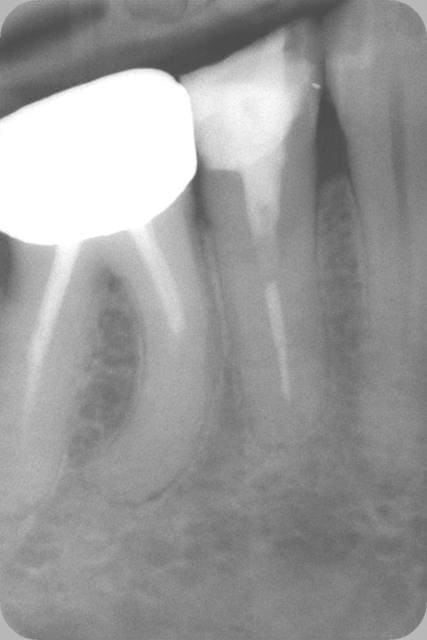

Voilà les radios : l'endo à l'amalgame dans la chambre de mon confrère (On notera aussi la belle endo sur la 6, courbure bien négociée par le confrère. Comment défendre ce type de boulot sur les 2 dents ?) et mon endo+RMIPP+compo à 139,70€.

Oui c'est pas au bout radiologiquement. A 80 ans c'est pas large, ça butait à la C+ 8/10èmes.

Le tenon fibré c'est la zone radioclaire au dessus, noyé dans le composite. On voit qu'il n'y a pas de gutta ni de ciment qui débordent.